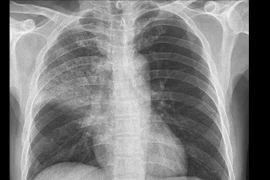

Điều trị thành công ca viêm phổi cộng đồng trên bệnh nhân xơ gan

Bệnh viện Đa khoa Vân Đình vừa điều trị thành công bệnh nhân nam 52 tuổi, viêm phổi cộng đồng nặng trên nền xơ gan, viêm gan B mạn và tiền sử lạm dụng rượu.